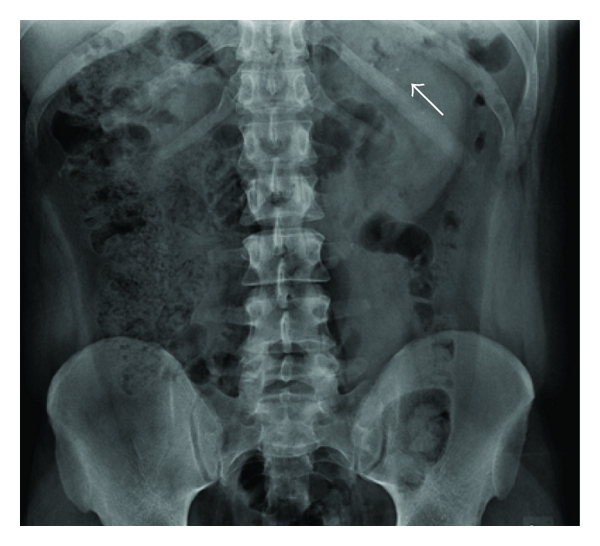

This characteristic difference in attenuation with dual-energy imaging (i.e., contemporaneous CT scanning at 80 and 120−140 Kv) may potentially allow accurate determination of stone composition which may facilitate more appropriate management in patients with uric acid (UA) containing calculi who may benefit from medical management and those with cystine and certain calcium stones which may be more resistant to shock wave lithotripsy [43] (see Figures 2–3).

(a)

(b)

(c)

(d)